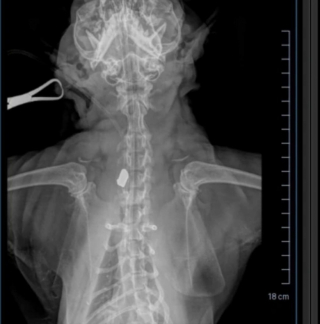

Jen s’est empressée de se rendre chez le vétérinaire pour en savoir un peu plus. Choqué lui-aussi, le professionnel a constaté que le chat avait été blessé par balle, visiblement volontairement. Malheureusement, la balle se trouvait toujours dans le cou du félin. Il fallait agir au plus vite pour écarter toutes complications.